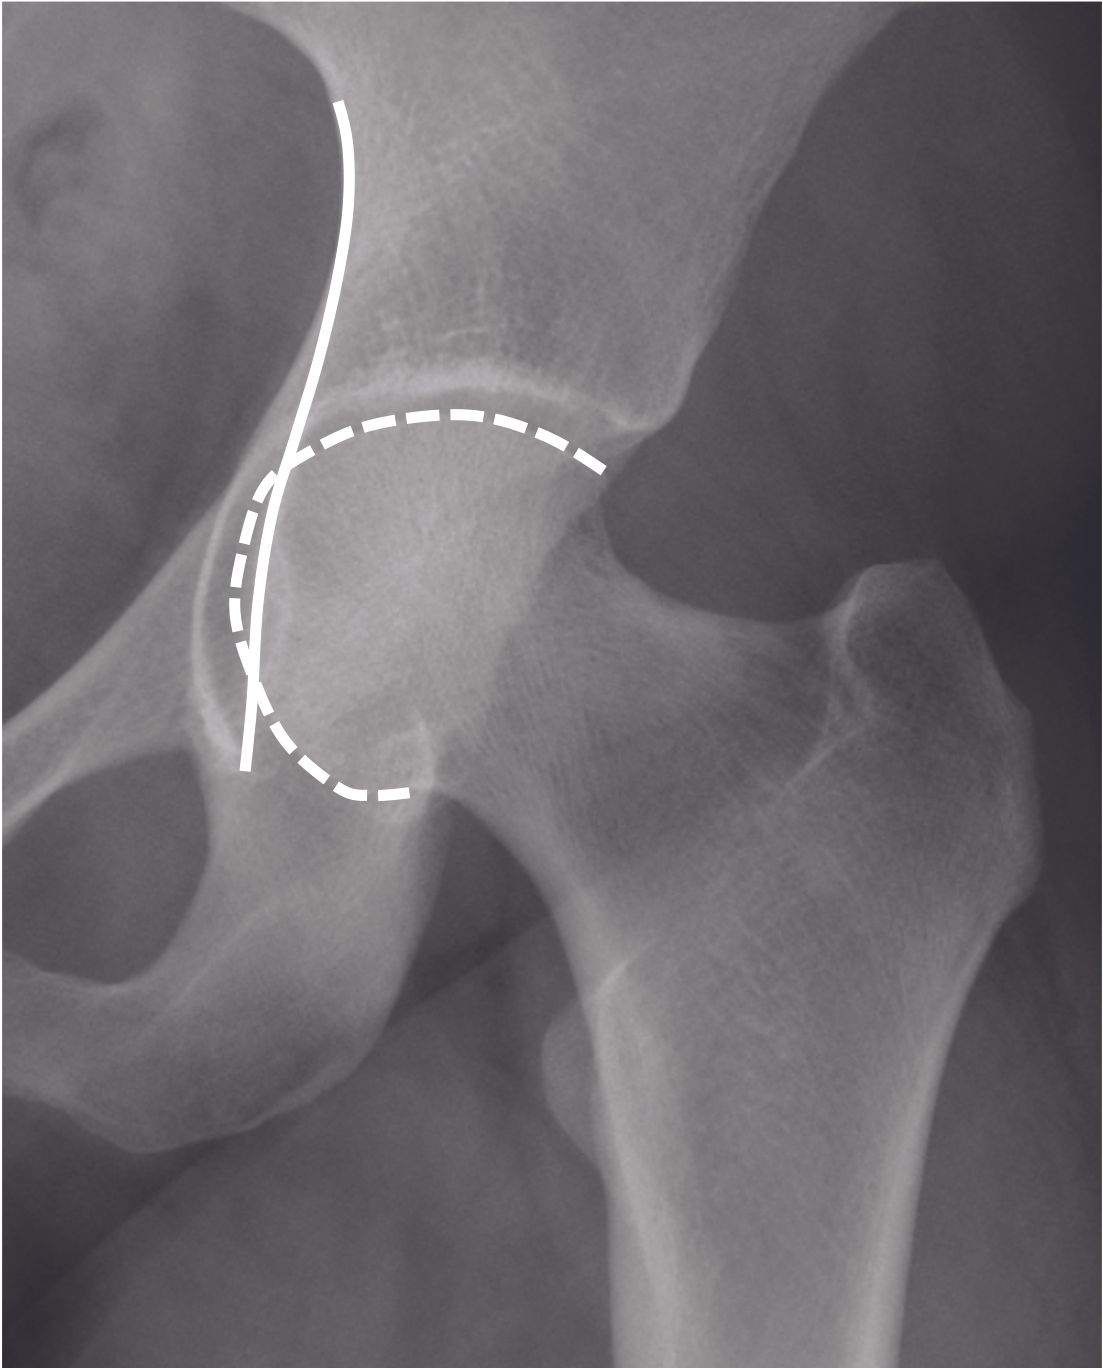

Excessive coverage of the acetabulum can lead to a pincer-type FAI. This is seen with a Wiberg Lateral Center Edge (LCE) angle greater than 33° (4) (Figure 2). Pincer-type FAI may also occur in cases of acetabular protrusion (Figure 3) when the femoral head is medial to the ilio-ischial line.

The orientation of the acetabulum is important to assess, as it can also be the source of a pincer-type FAI if the acetabulum is retroverted (Figure 4).

The retroversion of the acetabulum may be focal (<30%) or global (>30%) depending on the crossing sign size. Posterior wall sign (posterior wall medial to the center of the femoral head), and ischiatic spine sign (visible on front pelvic film beyond the iliopubic line) are the two other signs for acetabulum retroversion. The filling of the cervico-cephalic junction can cause a cam effect (Figure 5), sometimes with a pistol grip appearance. The cam effect can be quantified using the alpha angle measured on the axial radiograph.